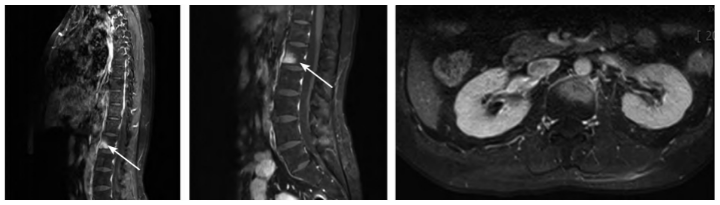

完善胸腰椎MRI增强扫描提示T6椎体及邻近附件、肋骨及L1椎体伴周围软组织异常强化影,考虑炎性病变(见图4、5)。

图5 胸腰椎MRI增强扫描。箭头所指为L1椎体,椎体前下缘见斑片状明显强化,邻近软组织可见强化

入院后结合其病史、临床表现及胸、腰椎MRI,初步诊断为脊柱源性疼痛综合征,但仍需明确胸腰椎异常信号的性质。完善全身骨显像

提示第5、6胸椎、第1腰椎见骨异常显像剂分布浓聚灶(见图3)。T5、T6、L1代谢增高,考虑炎性病变。

图3 全身骨显像。双侧胸锁关节、多发胸肋关节、L1椎体异常放射性摄取增高,可见“牛头征”